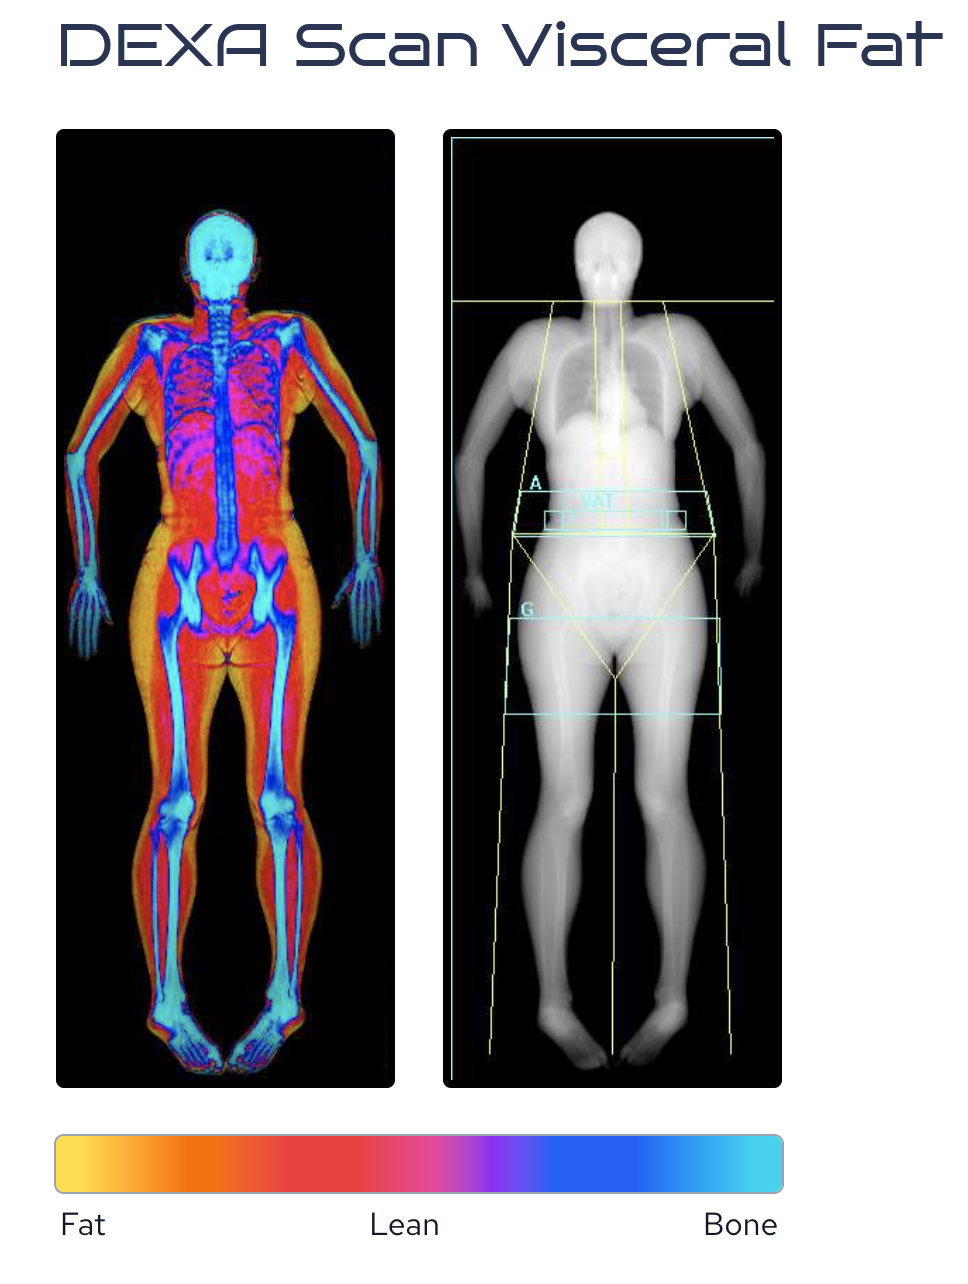

Identify health risks before disease develops through advanced blood testing, body composition analysis, and VO₂ max assessment.

Through advanced precision diagnostics we provide a deeper, more sophisticated understanding of your physiology and long-term health risks.

This includes:

advanced biomarker testing (such as detailed lipoprotein analysis and Lp(a))

body composition scanning,

VO₂ max assessment to evaluate cardiovascular fitness and performance.

These insights enable a highly personalised, preventative strategy — allowing us to detect early risk, optimise health, and support longevity at the highest level.